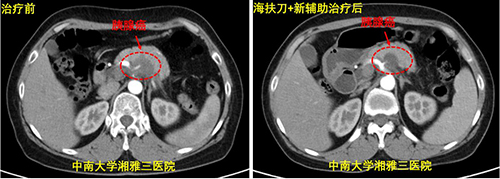

2021年11月9日,在主任余枭的指导下,陈浪博士在湘雅三医院海扶中心为该患者进行了针对胰腺病灶的海扶刀手术。海扶术后第一天,该患者的疼痛症状便基本消失,不再需要服用止痛药,生活质量较前明显改善,联合应用第一次化疗后满意出院。出院后患者于我院规律复查并定期接受新辅助治疗。复查CT显示该患者的胰腺低密度灶范围较前缩小,大部分坏死可能,血管受累情况较前明显改善。

新辅助治疗前后对比

考虑患者继续进行新辅助治疗意义不大,经过综合评估,行联合血管的胰腺癌根治性切除术可能对改善该患者预后具有一定价值。但该患者手术难度极高,术中稍有不慎,即可损伤腹腔内重要血管造成术中大出血,难以控制。在经过科内疑难病例讨论制定详细手术方案后,余枭教授团队与患者家属进行充分沟通,在得到患者及家属的充分信任后,团队对患者进行手术安排。4月18日,由肝胆胰II外科余枭教授、孙吉春副教授、钟方敬博士以及血管外科王征副教授组成的手术团队为该患者实施了胰体尾切除+脾切除 +腹腔干切除+门静脉部分切除修补术,手术顺利。术后病检示:胰体中分化导管腺癌,各切缘未见癌残留,胰周淋巴结未见癌转移,实现了R0切除。